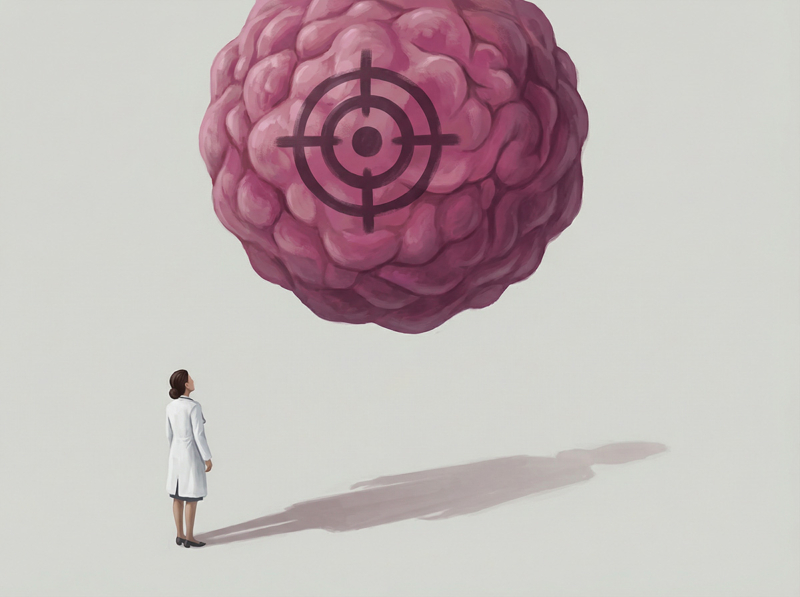

Wissenschafts- & Forschungskommunikation

Wir machen medizinische und wissenschaftliche Inhalte sichtbar – für Fachkreise, Entscheidungsträger und Öffentlichkeit.

Wir schaffen Visuals, die fachlich und visuell überzeugen – für Forschung, Ausbildung und Healthcare-Kommunikation

In unserer Galerie zeigen wir exemplarisch KI-basierte Bild- und Bewegtbildwelten aus verschiedenen Bereichen. Filtern Sie nach Themen – und sehen Sie, wie wir komplexe Inhalte in klare Visuals übersetzt haben.

Jedes Motiv ist ein Beispiel dafür, wie wirkungsstark KI-Bildproduktion und KI-Motion gezielt für Healthcare- und Wissenschaftskommunikation sein können.